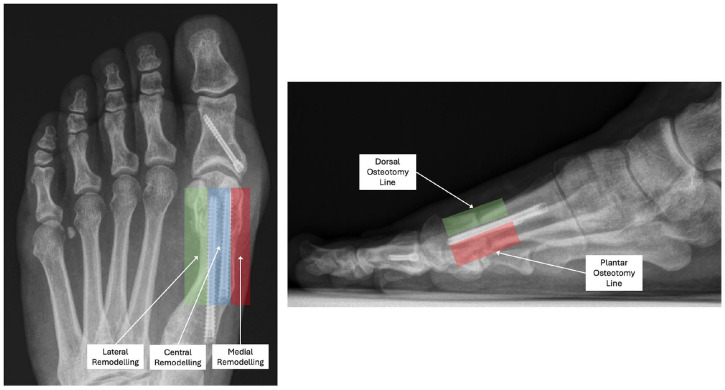

Methods: A 4-domain radiographic classification system based on callus formation, anteroposterior (AP) osteotomy line, lateral osteotomy line, and remodeling for MIS osteotomy healing was developed and tested on a cohort of 27 feet that underwent percutaneous transverse osteotomy for hallux valgus correction. Patients had simultaneous postoperative weightbearing computed tomography (WBCT) and standard radiographs following surgery. Five surgeons reviewed anonymized radiographs to evaluate interobserver reliability. WBCT was used to confirm union status and classification interpretation.